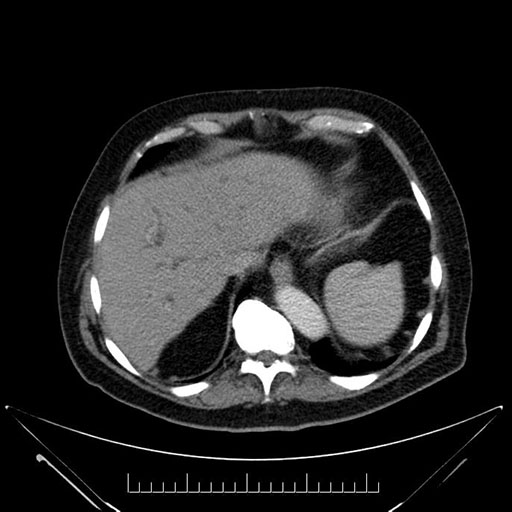

Whipple (pancreaticoduodenectomy) [case 7]

Imaging Analysis

Look through the patient's CT scan to identify any areas of concern for the necessary procedure.

Based on your CT findings, which issue(s) would give reason for "planned slowing down moment(s)" in this case?

Considering a standard Whipple procedure, what step(s) of the operation would you do differently in this case?